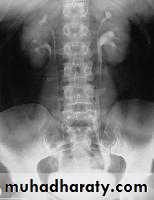

Congenital cystic kidney (polycystic kidney) (Adult cystic renal disease)

Autosomal dominant, transmitted by either parents, 50% of offspring affected.

Both kidneys replaced by large no. of cysts of variable size which make the kidney of large size.

The cysts contain clear fluid but sometimes blood.

The cysts progressively increase in size causing pressure atrophy of the renal parenchyma and pressing the ureter.

15% associated with cystic disease of liver, lung, pancreas or spleen.

Clinical pictures:

Rarely gives clinical manifestation before 4o years

Asymptomatic: diagnosed accidentally.

Pain: due to pedicle stretching, stone, ureteric obstruction, bleeding inside cyst or infection.

Hematuria: cyst distention and rupture to the collecting system.

Infection: renal or cyst infection causes fever, rigor and loin pain.

Hypertension: in 70%, Unknown cause.

Renal impairment: anorexia, headache, nausea, vomiting, drowsiness and coma.

Renal enlargement: large knobby palpable kidney

Diagnosis: Family history of polycystic disease.

U/S, IVU, CT scan, MRI